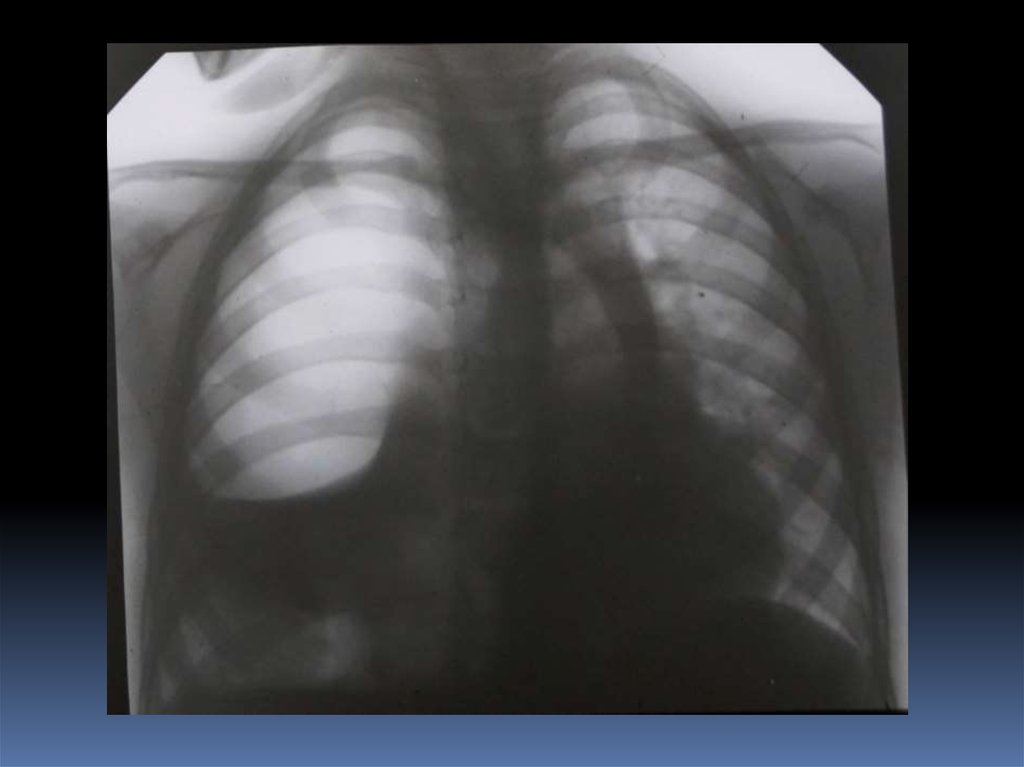

5. Проведение рентгеноскопического исследования раненого.

6. Проведение рентгенографического исследования раненого.

7. Виды травматического повреждения грудной клетки:

пневмоторакс;

гемоторакс;

гемопневмоторакс;

внутрилегочные гематомы;

дисковидные ателектазы;

посттравматические пневмонии.